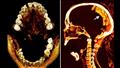

والآن، توصل علماء إلى تفسير لمومياء "المرأة الصارخة" بعد استخدام الأشعة المقطعية لإجراء تشريح افتراضي. واتضح أنها ربما ماتت وهي تتألم وعانت من نوع نادر من تصلب العضلات، يسمى تشنج الجثث ويحدث في لحظة الوفاة.

الباحثة سحر سليم، الأكاديمية المتخصصة في علم الأشعة بجامعة القاهرة، قادت دراسة نُشرت نتائجها في دورية "فرونتيرز إن ميديسين"، وتوصلت إلى إن الفحص يوضح أن المرأة كانت تبلغ من العمر نحو 48 سنة عند وفاتها، وكانت تعاني من التهاب خفيف في العمود الفقري وفقدت بعض أسنانها.